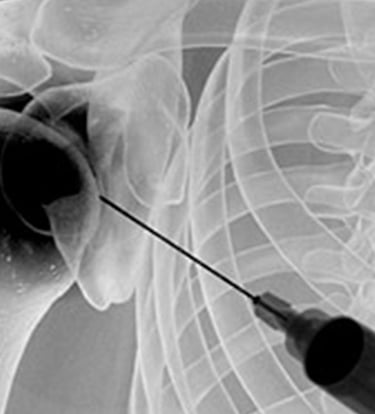

Gydytojas Markas Fiodorovas - ortopedas traumatologas, sporto traumų specialistas, sukaupęs 20 metų patirtį tausojančioje artroskopinėje chirurgijoje. Daugiau nei 650 artroskopinių kelio, peties ir kitų sąnarių operacijų per metus atliekantis chirurgas, taip pat aktyviai įsitraukęs į mokslinę veiklą. Gydytojas yra nuolatinis tarptautinių konferencijų lektorius bei tarptautinis artroskopinės chirurgijos instruktorius.

Gydytojas Markas Fiodorovas - ne tik vienas daugiausiai operuojančių ortopedų - traumatologų Lietuvoje, bet ir aktyvus mokslinės bendruomenės narys, lektorius bei instruktorius. LASTA ir ESKKA asociacijų narys, nuo 2010 metų nuolat skaito pranešimus tarptautinėse konferencijose. Tarptautinis artroskopinės chirurgijos kursų instruktorius nuo 2012m. moko artroskopijos chirurgus visame pasaulyje.